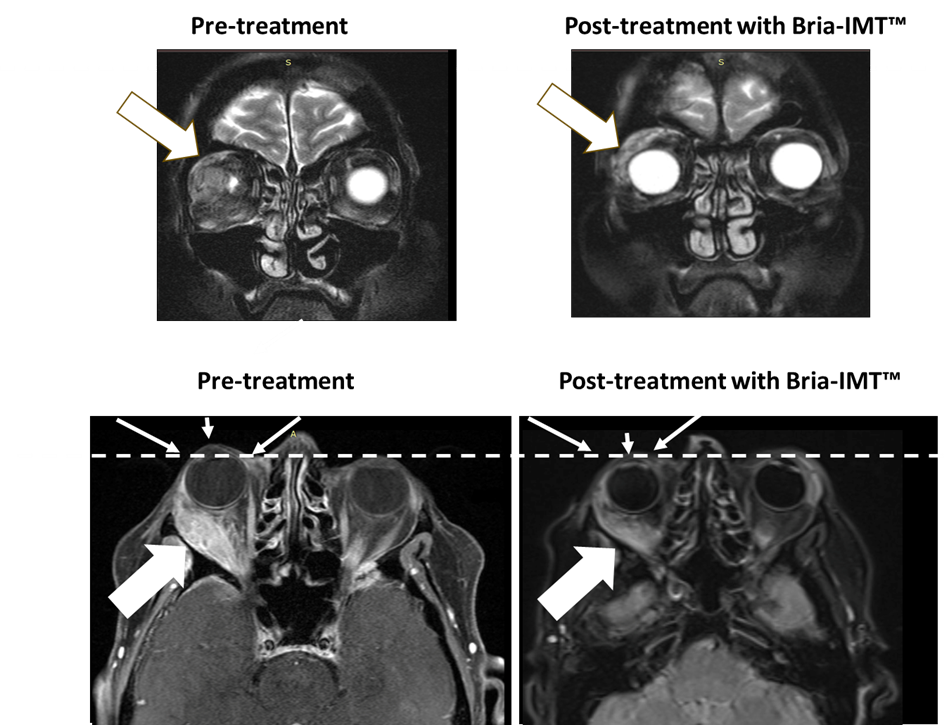

The following figure shows magnetic resonance imaging (MRI) of the orbital tumor. The top left MRI image shows the tumor in the right orbit behind the eye with the eye not being visible pre-treatment. After treatment with the Bria-IMT™ regimen, the eye becomes visible (top right image) as it has regained its normal position. In the lower images, the dashed line represents normal margin of eye position with resolution of proptosis post treatment (small arrows) with the Bria-IMT™ regimen. Reduction in tumor is represented by large arrows.

Magnetic resonance imaging (MRI) of the orbital tumor. The top left MRI image shows the tumor in the right orbit behind the eye with the eye not being visible pre-treatment. After treatment with the Bria-IMT™ regimen, the eye becomes visible (top right image) as it has regained its normal position. In the lower images, the dashed line represents normal margin of eye position with resolution of proptosis post treatment (small arrows) with the Bria-IMT™ regimen. Reduction in tumor is represented by large arrows.